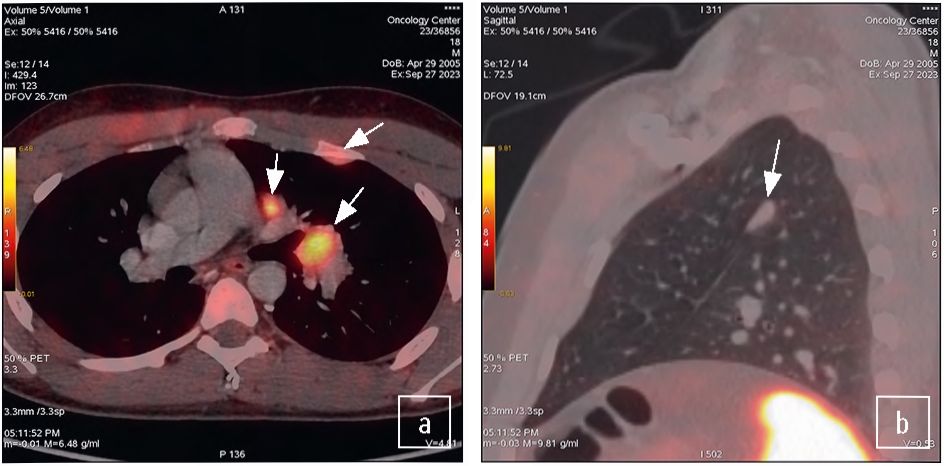

Рис. 2. ПЭТ/КТ с 68Ga-DOTA-TATE. Рецидив НЭО тимуса, образования с признаками накопления РФЛП (стрелка). Один из очагов (b) – без признаков накопления РФЛП (стрелка).

Fig. 2. PET/CT with 68Ga-DOTA-TATE. Recurrence of a neuroendocrine tumor of the thymus; a mass with signs of increased radiopharmaceutical uptake (arrow). One of the lesions (b) has no signs of increased radiopharmaceutical uptake (arrow).

В июле 2023 г. пациент отметил ухудшение общего самочувствия, появление стрий на внутренней поверхности бедер, ягодицах, одутловатость лица, увеличение массы тела на 12 кг за 6 мес, повышение артериального давления до 164 и 90 мм рт. ст. По данным ПЭТ/КТ с 68Ga-DOTA-TATE (рис. 2) от 27.09.2023 выявлено наличие патологической ткани с гетерогенной невысокой активностью 68Ga-DOTA-TATE в средостении, корне левого легкого, узловом образовании вдоль костальной плевры (в SIII) слева и в парамедиастинально расположенном очаговом образовании по междолевой плевре слева.